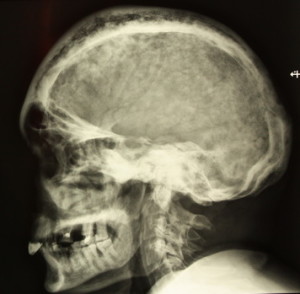

Выявить остеит можно только при помощи рентгенологического исследования. Впрочем, желательно осуществить повторный рентген для того, чтобы уточнить диагноз. Проводится консервативное лечение с соблюдением постельного режима. Лечение осуществляется на протяжении месяца. Если же пациент обратился с заболеванием в запущенной стадии, то необходимо осуществить хирургическое вмешательство.

У многих больных наблюдается поражение костей именно в области позвоночника. Впрочем, иногда наблюдаются поражения и в костях черепа, а также таза. Симптомы болезни Педжета – сильная боль, деформация костей. Чаще всего, остеит возникает из-за переломов.

При возникновении данного заболевания обычно симптомов не наблюдается. Выявить точный диагноз сможет только доктор при рентгенологическом исследовании. При осмотре могут быть замечены выпуклый лоб или искривление ног. Из-за сильного кровотока в пораженных участках наблюдается покраснения, а также повышение температуры. Хоть данное заболеванием не протекает с воспалительным процессом, но его называют «деформирующим остеитом».